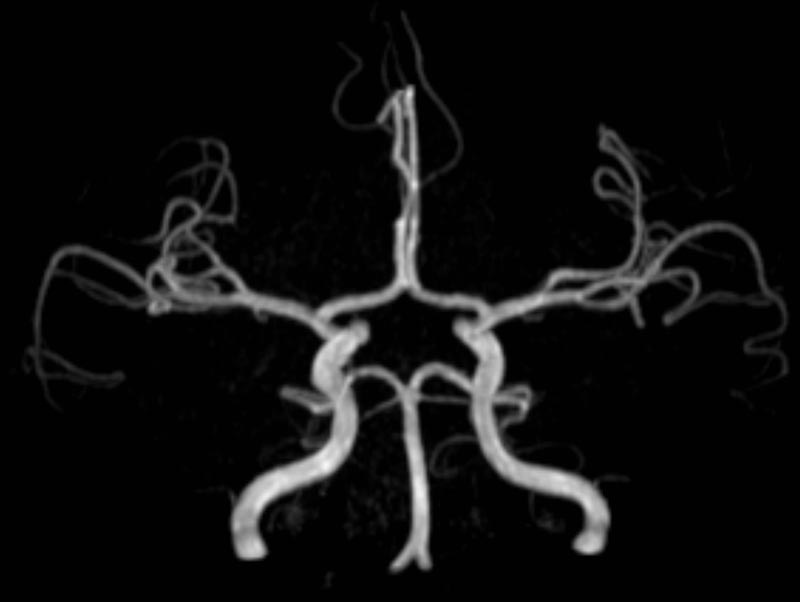

- MR-Angiografie ohne Kontrastmittel

- Time of Flight (TOF)-Angiographie

- Phasenkontrastangiographie (PCA). Geeignet zur Quantifizierung Stenose-/Insuffizienzgrad z.B. bei Herzklappen, falls echokardiographisch die Untersuchungsbedingungen eingeschränkt sind.

Je nach Fragestellung und Körperregion Gefäßdarstellung ohne Kontrastmittel bei Kontrastmittelunverträglichkeit oder terminaler Niereninsuffizienz möglich.

- MR-Angiographie mit Kontrastmittel

- Erfassung arterieller und venöser Gefäße/Bypässe aller Körperregionen mit 3D-Rekonstruktion

- je nach klinischer Fragestellung zeitaufgelöste MR-Angiographie (4D-MRA) z.B. bei Frage arteriovenöse Fistel/ Shunt oder Darstellung Unterschenkelarterien vor geplanter Bypassoperation.